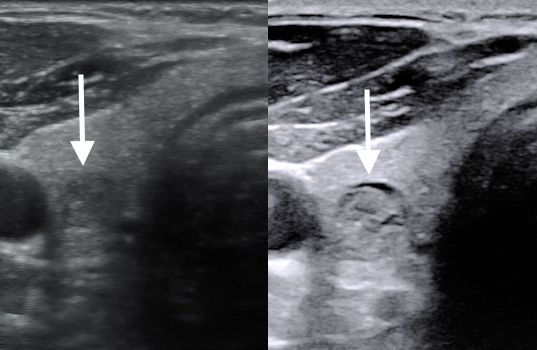

Zapraszam do zapoznania się z relacją filmową z zabiegu leczenia etanolem guzka płynowego tarczycy wraz z opisem metody i wyjaśnieniami. Zabieg został przeprowadzony w Szpitalu na Klinach.

Wykonuję zabiegi leczenia guzków tarczycy małoinwazyjnymi metodami: laserowej termoablacji (EchoLaser) i przezskórnego leczenia etanolem.

Zabiegi oraz badania USG tarczycy oraz biopsji cienkoigłowej celowanej tarczycy (BACC) są wykonywane przy pomocy technik wspomagających, jak elastografia, oraz wizualizacja igły biopsyjnej.

Kolejna moja wizyta związana z leczeniem guza na tarczycy. Zabiegi polegają na ewakuacji płynu i podawaniu stężonego etanolu do guzka, alternatywa to wycięcie płata tarczycy ale Pan doktor walczy i wyjaśnia że to ostateczność. Pan doktor wyjaśnił wszystkie za i przeciw, jest konkretny. Dziękuje Panie Doktorze